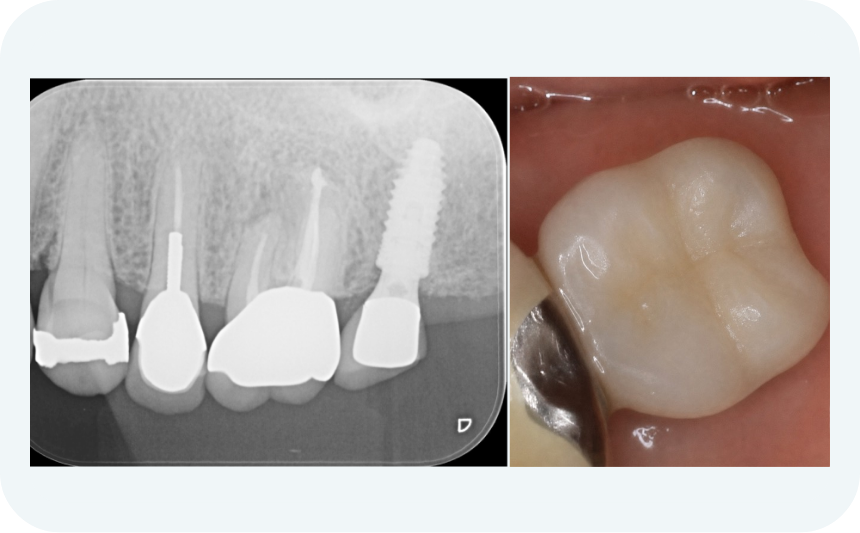

BEFORE

奥歯を抜歯し、噛みにくい

奥歯を抜歯し、噛みにくい

部分入れ歯に違和感

部分入れ歯に違和感

見た目も気になるとの相談

見た目も気になるとの相談

AFTER

自然な見た目で、噛みやすさが大幅に改善

自然な見た目で、噛みやすさが大幅に改善

「硬いものも問題なく噛めるようになった」との声

「硬いものも問題なく噛めるようになった」との声

| 治療内容 | 奥歯1本のインプラント+セラミッククラウン |

|---|---|

| 治療期間 | 約5ヶ月 |

| 費用 | 約35万円(税込) |